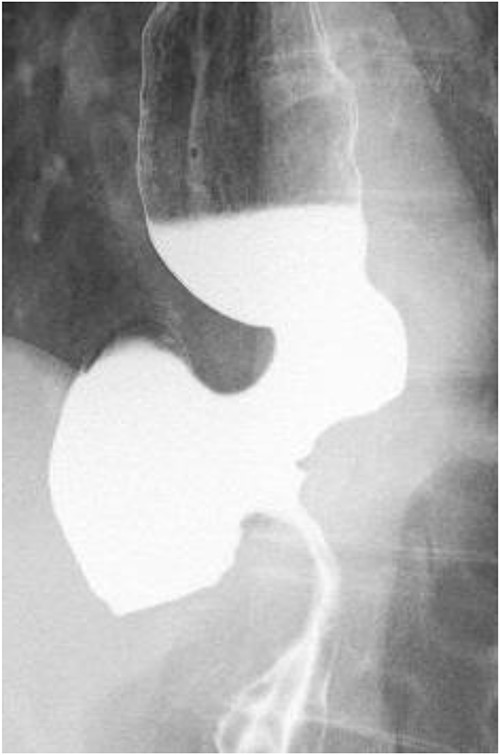

A 60-year-old female with dysphagia and vomiting visited the university hospital. In 2007, she underwent esophageal diverticulum resection (procedure unknown) with a diagnosis of an esophageal diverticulum, which subsequently recurred. In 2011, she underwent a transesophageal hiatus diverticulectomy and a fundoplication (Nissen procedure) at a local hospital. In 2013, dysphagia and vomiting appeared. The patient was diagnosed with recurrence and underwent balloon dilatation for follow-up. In 2015, the patient came to our hospital due to persistent symptoms. After one balloon dilation, the patient did not show any improvement and was referred for surgery. Esophageal fluoroscopy revealed a diverticulum 5 cm in size in the lower esophagus just above the eruption. There was no significant change in the diverticulum size before and after dilation (Figs 1 and 2). Gastrointestinal endoscopy revealed a diverticulum in the lower esophagus, with a residue accumulation (Fig. 3). The esophagus directly below the diverticulum was narrowed. The patient was diagnosed with recurrent lower esophageal diverticulum and underwent surgery.

Upper digestive tube endoscopy. The esophagus just below the diverticulum was stenotic, and there was residue accumulation in the diverticulum.